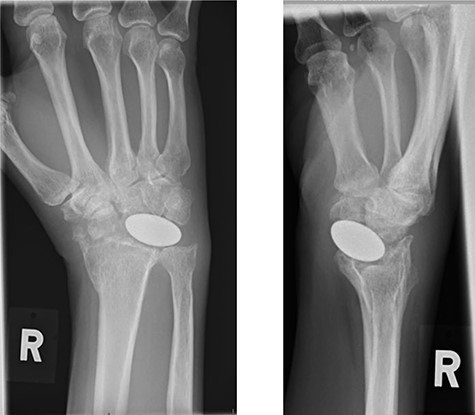

A 50-year-old, right-hand-dominant woman, presented with a history of stiffness and pain affecting her right wrist, associated with a history of increasing swelling on its palmar aspect. She had been treated for post-traumatic arthritis of the same wrist 7 months earlier by arthroplasty with a Pyrocarbon Amandys implant; she also reported gradual onset of tingling sensations in her ring finger. She had an initial uneventful recovery but developed clinical symptoms of carpal tunnel syndrome 2 months later, with paresthesia in the right thumb and index finger radiating to the forearm, which was worse at night. A diagnosis of carpal tunnel syndrome was confirmed by nerve conduction studies. Post-operative radiograph at this time showed the pyrocarbon implant in an adequate position (Fig. 1).

X-rays of the right hand showed palmar displacement of the pyrocarbon implant.